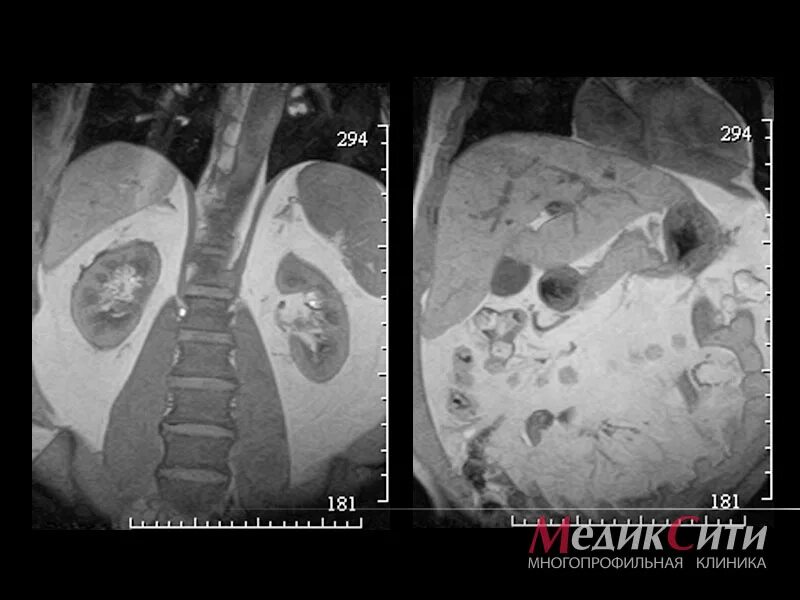

Камни в желчном мрт